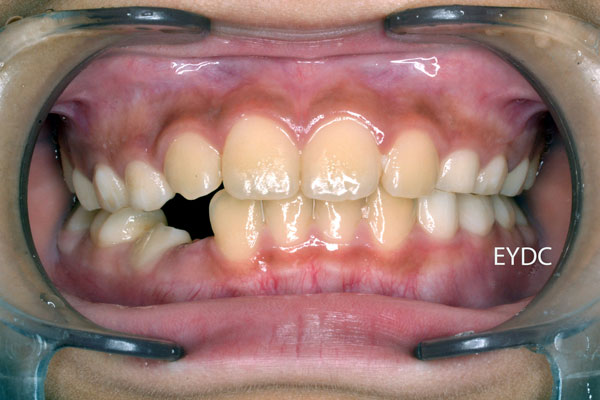

受け口は治りましたが、デコボコしています。仕上げに前歯だけにブレースとワイヤーを装着します。11才2ヶ月です。

1期矯正の完成です。お母様の熱意の賜物です。ご希望のご家族は2期矯正に進みます。13才0ヶ月でした。歯並び育成期間6年11ヶ月です。